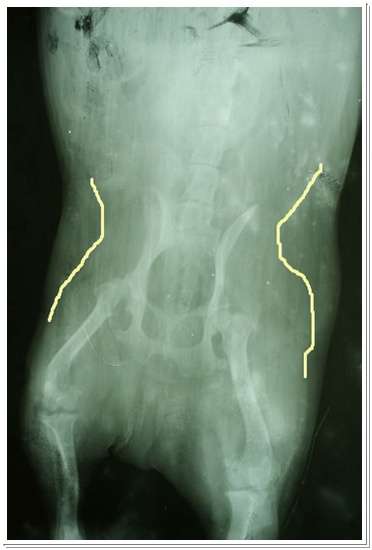

周醫生說這X光片雖然拍的不是很好,看出來江GO天生就有髖關節的問題,程度屬於中下...不用重照!

而且,從X光片看來,江GO的右腳並沒有萎縮的很明顯,骨頭外的肌肉也十分的飽滿...

下面黃色線內的都是肌肉的部份,之外的都是油....